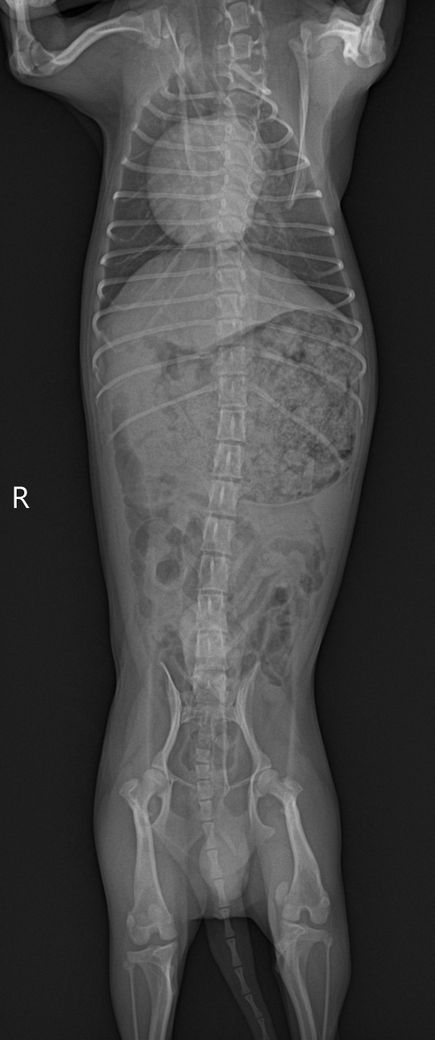

담당 의사선생님께서 십자인대의 문제는 확인이 어렵다고 하셨는데, 보통 X-ray로 확인하지 않나요..?ㅠㅠ 그래서 아하에 계시는 수의사 분들께 병원에서 받아온 X-ray 사진과 병원에 진료 후 내려놨을 때 걷는 영상을 첨부하오니, 100%가아니더라도 십자 인대 수술이 필요해보이는지, 다른 소견은 없는지 등의 진단을 부탁드립니다..!ㅠㅠ

30cm가 이니라 10여도 터질 십자인대는 터집니다. 다만 첨부한 사진에서 양쪽 뒷다리의 측면 사진이 모두 첨부되어야 관절낭을 중심으로 비교 평가할 수 있는데 사진이 누락되어 판단할 수 없습니다. 다만 주관적으로 2번째 첨부 사진에서 아킬레스건의 부종 양상이 관찰되고 슬개골 관절낭의 심한 종창은 보이지 않아 십자인대 단열보다는 아킬레스건 부분단열을 먼저 고려해야 할것으로 보입니다. 주치의의 지시에 따라 평가 진행해도 크게 무방합니다.